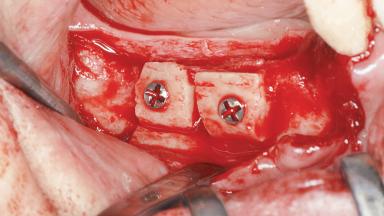

A woman in her mid-fifties was referred by a dental student for dental implant placement. Both posterior segments of the mandible had been edentulous for more than 4 years, the only residual tooth being the right lower first premolar. The patient had used a removable partial denture but was not entirely satisfied with its function. The clinical examination revealed a sharp edentulous ridge in both posterior segments of the mandible, and the patient was told that it would not be possible to insert implants into this thin edentulous ridge without significant augmentation of the alveolar ridge. Her medical history revealed no significant findings and no underlying disease that might have complicated surgical procedures. During the presurgical examination, the patient reported that she was a little apprehensive about bone grafting. After being informed about the surgical procedures and potential postoperative complications, she accepted the proposed surgical plan of bone grafting and subsequent placement of implants.

Bone Augmentation Horizontal|Staged

Augmentation Materials Autogenous block(s)|Xenogenous|Membrane

Bone Volume Deficient horizontally, requiring prior grafting